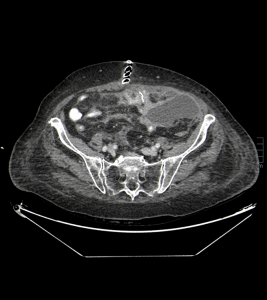

Posteriormente, se realiza un control tras 4 días a partir del momento de la colocación del catéter de drenaje, gracias al cual se obtienen las siguientes imágenes:

Haz click en las imágenes para verlas ampliadas

Se realiza estudio de TC abdominopélvico con contraste oral, se compara con anterior, apreciándose, mejoría, con resolución prácticamente total de la colección de FI izquierda, visualizándose el catéter pig-tail, bien posicionado. No se evidencia dilatación de asas intestinales, se visualiza transito intestinal conservado sin extravasación del contraste.